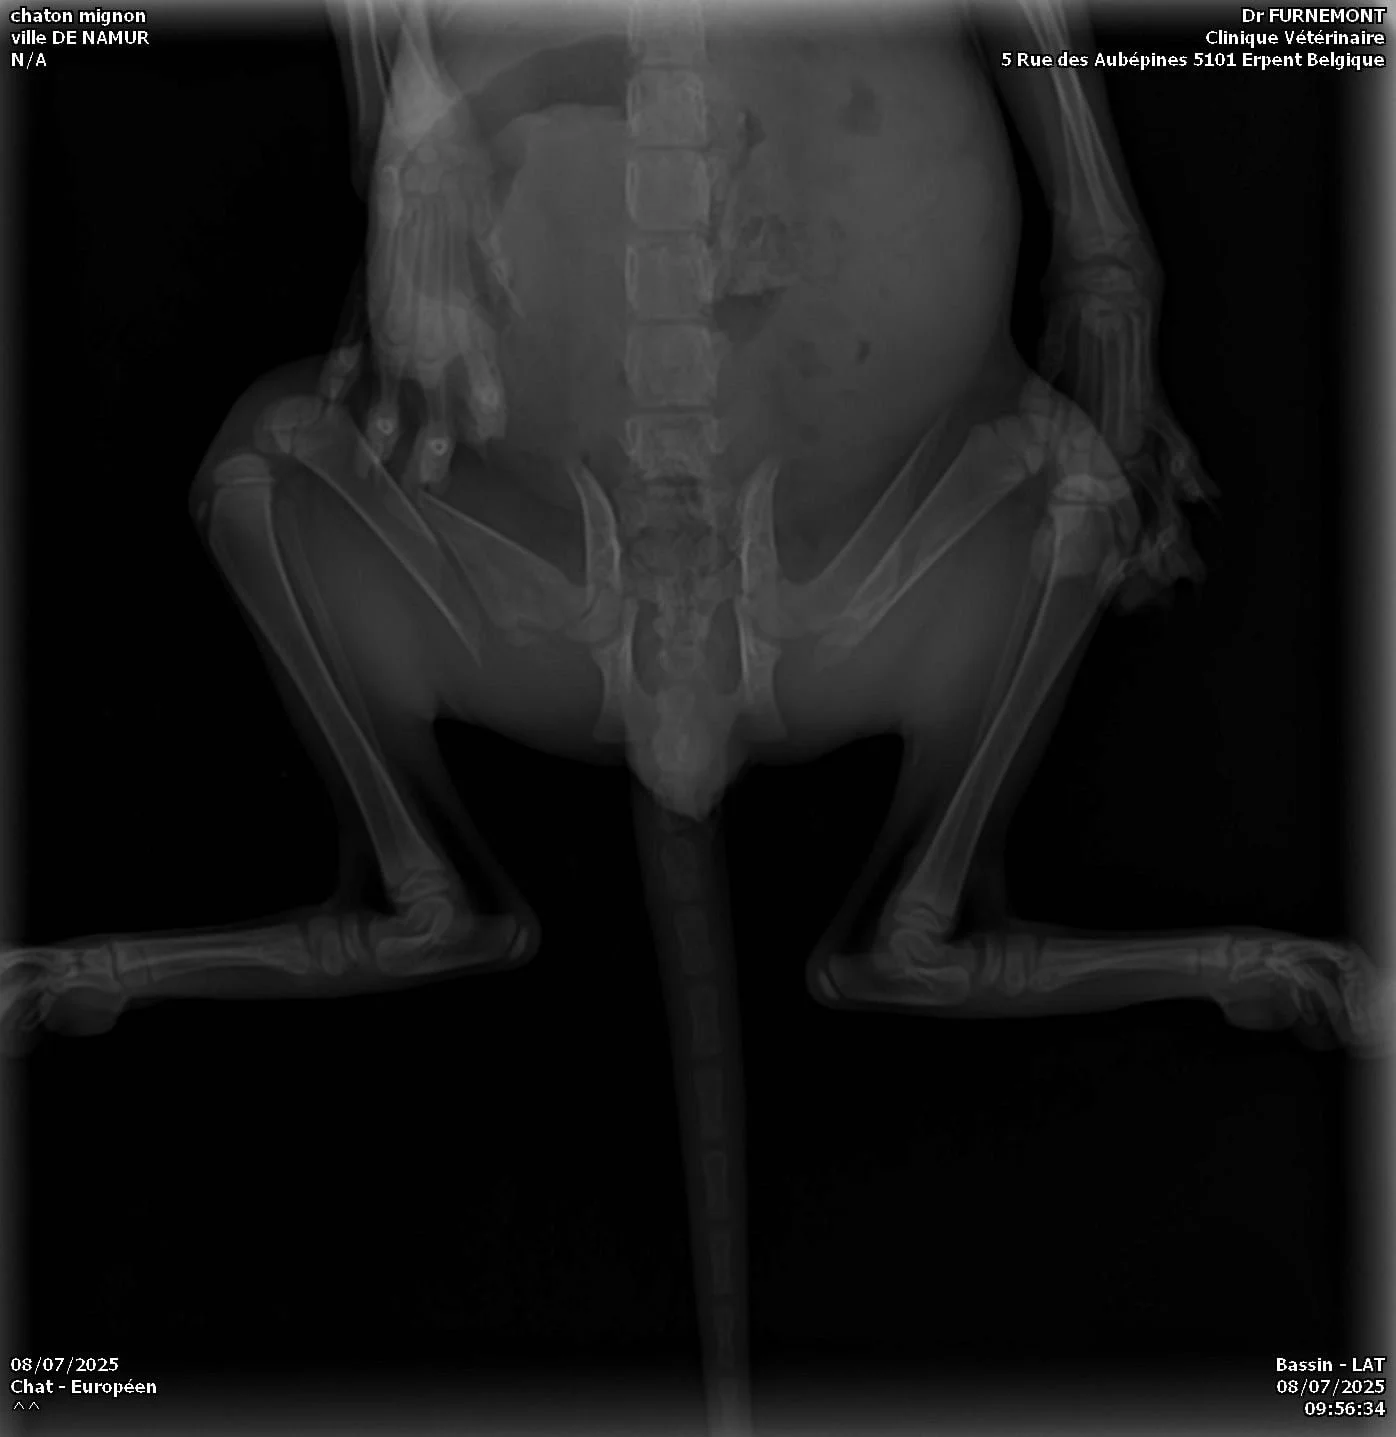

Buzz est arrivé chaton au refuge et a eu des soucis urinaires qui se sont révélés plus grave que prévus. Une malformation et un problème urinaire qui s’est amplifié en grandissant.

Ne sachant plus uriner, Buzz a du être hospitalisé. Il a du subir une urétrostomie terminale. Ce qui consiste à amputer le pénis et ouvrir l'urètre sur une zone plus large pour faciliter la miction.